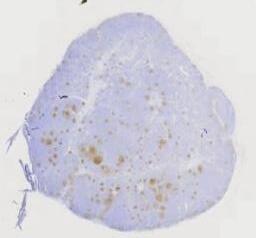

临床资料: 男,54岁,发现颈部两处肿物1年。双侧颈部局部探查:局部皮下软组织结构层次清晰,右侧颈部内可见一大小约24×8mm的淋巴结样回声,边界清,内回声不均匀血流信号,上述部位未见明显异常血流信号距体表约5mm。左侧颈部内可见数个淋巴结样回声,边界清,内回声不均匀,其中一个大小约6×5mm。CDFI:上述光团内及周边未见明感检查结果:双侧颈部软组织层异常占位(考虑淋巴结增大)。

大体所见: 灰白组织2枚,直径1.8-2.5cm,切面灰白。

免疫组化: 免疫组化:Ki-67(+),CD1O(+),CD20(+),Pax-5(+),CD3(+),CD5(+)。CD23(FDC网),Bcl-2(+),Bcl-6(+),MUM1(+),CD21(FDC网),CyclinD1(-),CD43(+),S-100(+),CD68(+).